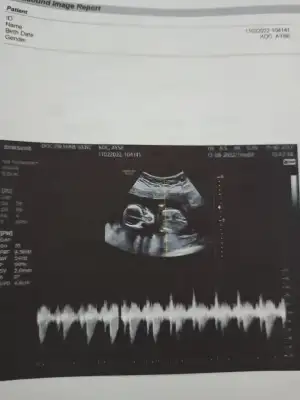

ozele gidiyorum aslında kizlarda 12. haftdada bende öğrenmiştim kesin konusmuslardi o zaman usg var ekliyorum yorumlarsanız sevinirim en azından kafam rahatlasin istiyorum ikilemde kalmak kötü hissediyor

Canım apış arası pek

görünmüyor sanırım dr da bu yuzden bekleyın demıs

Renkli usg ye doktor bisey demedi mi bacaklarını toplamış gibi tam anlaşılmıyor

bacak arası hep sim siyah renkli olanda da bulanık anlayamadık doktorda o yuzden emin olamadı. sanırım daha bekletmek istiyor biraz daha merak edin diyor 😀hayırlısı nasılsa oyle olsun inşallah sağlıkla hayırla dogsunlar bütün bebekler